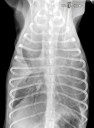

Quel est votre diagnostic ?

RadioQuiz 33 – Roméo n’a pas attaqué le facteur ce matin

RadioQuiz 32 – Oscar n’est plus le même docteur…

RadioQuiz 31 – Chien qui boite

RadioQuiz 30 – C’est parce qu’il fait frette que mon pitou tousse docteur ?